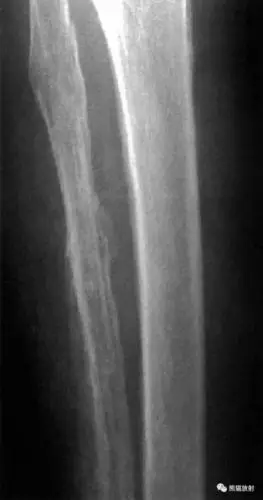

【读片】双侧四肢骨对称性骨膜增生,见过就难忘,结果已发 [病例帖]

一例原发性厚皮性骨膜增生症骨显像病例分析

骨膜增生厚皮症

增厚,密度增高,提示软组织肿物;食指近,中节指骨桡侧明显的骨膜增生

骨膜增生骨膜反应periostealreaction